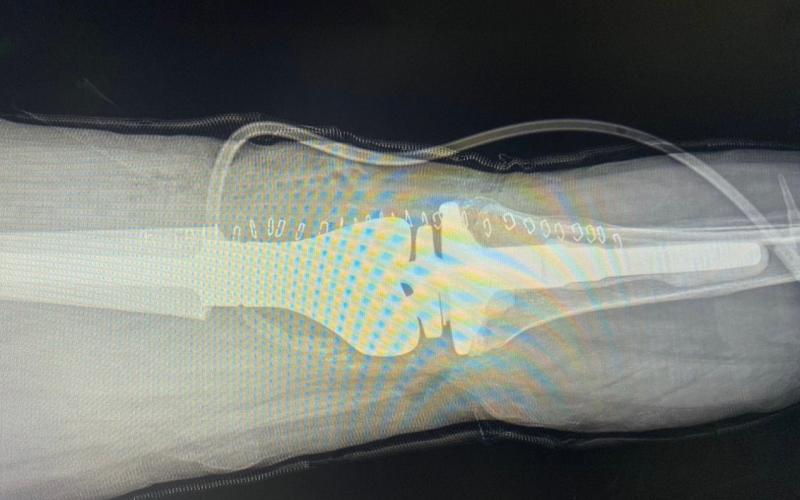

Recientemente, este centro asistencial, llevó a cabo con éxito su primera cirugía de revisión de prótesis de rodilla de este 2023. La intervención quirúrgica se realizó en una paciente de 63 años a la que se le colocó una prótesis tumoral.

"La paciente vino por un dolor en la rodilla izquierda en la que hace 9 años tuvo una sustitución con una prótesis que le fue colocada por un desgaste del cartílago articular. Le hicimos radiografías, una tomografía y documentamos un desgaste del implante con un desgaste del fémur distal, también se documentó rodilla de charcot", explicó el Dr. Soch.

"Tras el diagnóstico el equipo médico decidió realizar una revisión de la prótesis primaria que tenía la paciente y se le colocó una prótesis tumoral", agregó el profesional.